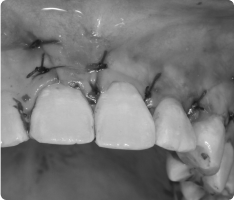

- 국소마취 후, 치아가 묻혀 있는 잇몸을 작게 열어 치아 머리(치관)를 노출시킵니다.

- 치아 표면에 교정용 버튼(장치)을 부착하고, 교정력(작은 고무줄·와이어)을 이용해 치아를 이동시킵니다.

- 수술 자체는 짧고 안전하게 진행되며, 이후에는 교정치료와 병행하여 서서히 치아가 배열됩니다.